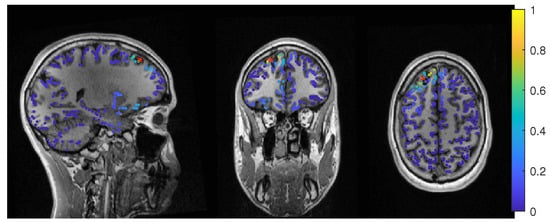

In Figure 11, the MEEG average-based beamformer localization at 0.05 regularization strength is presented.

The 6C event-related beamformer’s (bf-evt-6C) results show a similar behavior for MEEG as for the EEG. For low regularization up to a parameter of 0.048, the distance to the resection volume was 3 mm. For higher parameters, the distance jumped to 24 mm, with a fast increase in certainty. The 3C model showed similar results, although it could localize inside the resection for a range of parameters and the increase in its distance only happened at a higher regularization parameter of 0.09.

The MEEG average-based beamformer for both head models (bf-avg-6C and bf-avg-3C) showed a comparable performance as for single modality EEG and MEG. For both head models, distances to the resection volume decreased with increasing regularization strength and stabilized at a distance of 8 mm for regularization parameters above 0.03. Their relative power was almost identical and rather high.